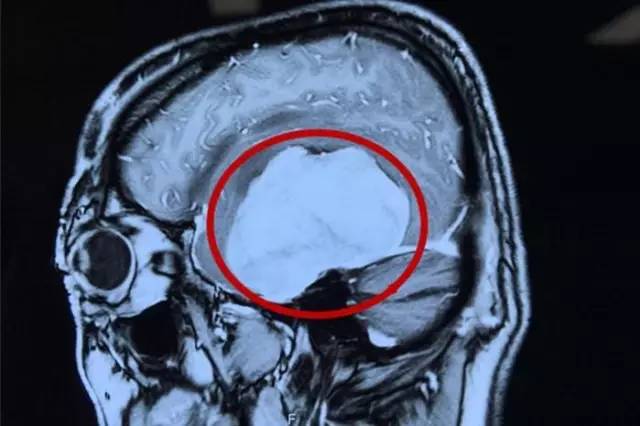

术前影像资料:红圈内白色部分为肿瘤物

这名患者叫虞文军(化名),57岁,浙江宁波人。三个月前虞文军右侧手臂肘部至肩部出现酸痛,上举无力,持续时间不长后缓解,因此便没在意。半个月前,虞文军在开车时再次突然出现手臂酸痛无力症状,致使方向盘失去控制发生车祸连撞三车,所幸并无人员伤亡。虞文军这才意识到问题的严重性,至当地医院就诊,行头颅CT检查示:左侧颞区底部大脑凸面可见类圆形略高密度占位病变,周围见低密度水肿影,CT值为44HU,大小约为8*6cm,周边脑组织及脑室受压,中线结构右移,额顶部软组织肿胀,考虑为左侧底部脑膜瘤。

为求进一步治疗,经过四处打听,虞文军在爱人的陪同下于4月22日前来我院就诊。我院神经外科专家潘仁龙主任接待了虞文军。入院后行头颅MR+增强及MRA发现:肿瘤供血丰富,供血起源于小脑幕上动脉。